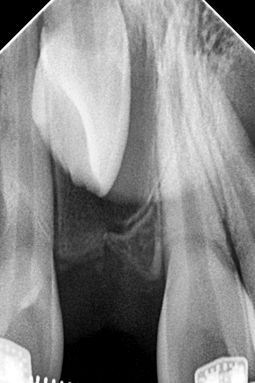

Una vez finalizado el proceso de tracción y alineación del incisivo 1.1, se retiró la aparatología fija empleada para la técnica (Fig. 27), se evaluó la vitalidad pulpar con cloruro de etilo en spray, dando una reacción positiva. Para el control radiológico se tomó la Rx periapical (Fig. 28) con el propósito de verificar el estado del hueso circundante en el ápice. Nótese en dicha radiografía un halo radiolúcido circundante a la raíz del incisivo 1.1, propio del proceso de aposición de hueso alveolar cercano a un diente traccionado.

Fig 27. Fotografía post retiro de aparatología fija - Fig 28. Rx periapical N4

Fig 27. Fotografía post retiro de aparatología fija

Fig 28. Rx periapical N4

Después del retiro de ortodoncia interceptiva para realizar la tracción del IC 1.1, se realizó un control a los 6 meses para verificar los resultados del tratamiento. En esta cita se hizo una prueba de sensibilidad pulpar con cloruro de etilo con respuesta positiva, una radiografía periapical de control (Fig 29) así como la fotografía intraoral de frente (Fig 30) y un escaneo digital (Fig 31 y 32 ). En la radiografía periapical se observa ya un proceso de formación de hueso alveolar alrededor de la raíz del diente traccionado, incluida la formación de lámina dura como cortical alveolar.

Fig 29. Rx periapical N5 - Fig 30. Fotografía de control 6 meses después de retiro

Fig 29. Rx periapical N5